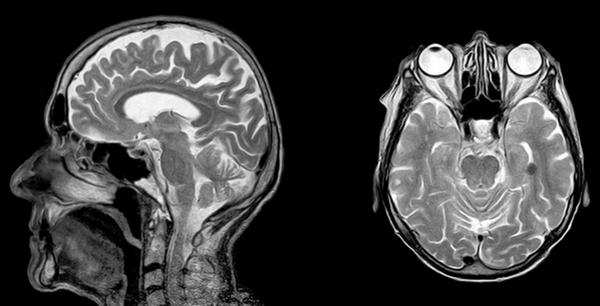

На рисунке - тазовое предлежание плода, 26 недель. Нормальная анатомия головного мозга

На рисунке - плод, 38 недель. Структурные изменения головного мозга плода не выявлены. Определяется однократное обвитие пуповиной

Диагностика мальформаций мозолистого тела по данным УЗИ часто представляет сложности. При этом результаты МРТ-исследования уже на 20 неделе гестации сравнимы с данными МРТ в постнатальный период.

На рисунке - плод, 29 недель. Агенезия мозолистого тела. Асимметричная гидроцефалия

МРТ плода позволяет диагностировать такие нарушения нейрональной миграции, как лисэнцефалия, гетеротопия, шизэнцефалия, мало доступные для диагностики при других методах исследования.

На рисунке - плод, 32 недели; поперечное положение плода. Шизэнцефалия